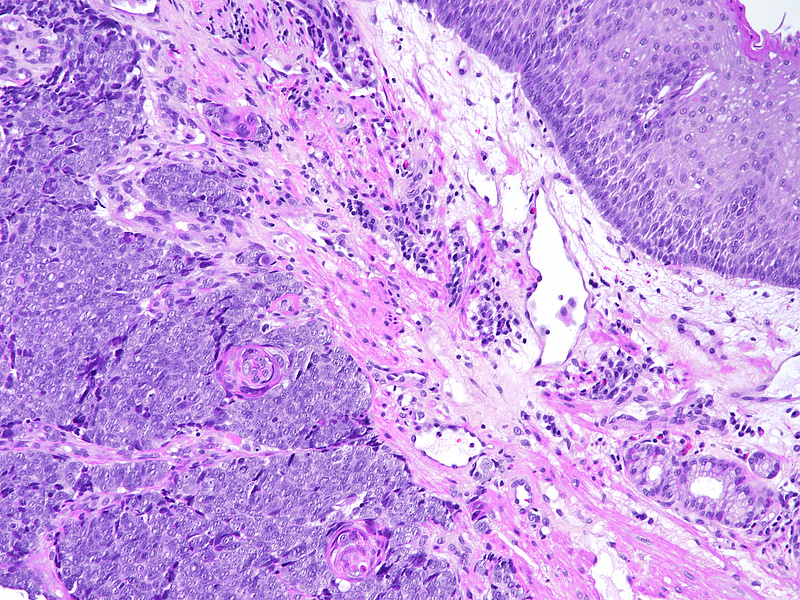

On low power the lesion is composed of sheets of monomorphic, overlapping small to medium sized malignant cells with irregular nuclear contours and finely dispersed chromatin without well-formed nucleoli (Panels A-B). Within these sheets of cells are demarcated areas of squamous differentiation, with formation of clearly visible squamous eddies and focal high-grade cytology (Panels C-D).

The immunohistochemical staining shows that the sheets of monomorphic cells show immunoreactivity for CD56 and synaptophysin (Panel E) and have a high proliferation index on ki67 staining (Panel F) proving neuroendocrine differentiation (neuroendocrine carcinoma, NEC). Of note, both areas of neuroendocrine and squamous differentiation show diffuse nuclear p40 immunoreactivity (Panel G) while cytokeratin positivity with CK5/6 is restricted to areas of squamous differentiation visible already on H&E, indicating more mature cells (Panel H). This reciprocal immunoprofile, taken together with the biphasic morphological pattern described above, is that of a mixed neuroendocrine-non-neuroendocrine neoplasm (miNEN).